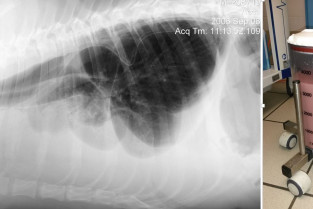

L’objet de cette journée est d’approfondir ses connaissances relatives au traitement du chylothorax chez le chien et le chat, en exposant l’état des lieux des connaissances actuelles en anatomie, imagerie et techniques chirurgicales.